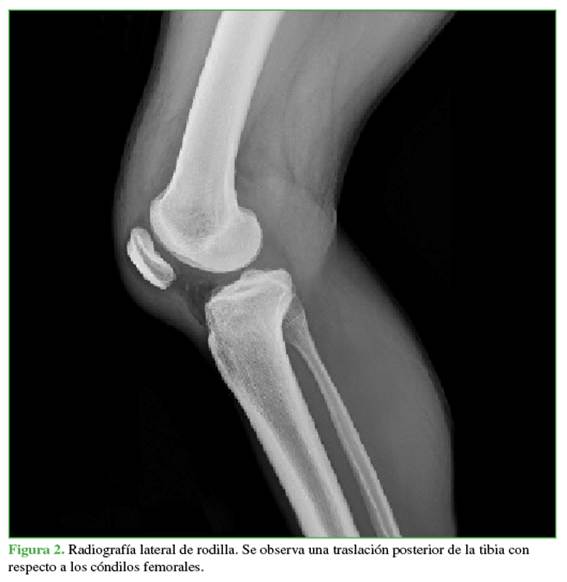

Hombre de 27 años, agricultor y residente en un área rural, sin antecedentes patológicos relevantes. Sufre un accidente de tránsito al caer por un abismo mientras conducía una motocicleta, lo que le provoca un traumatismo en el hombro y la rodilla derechos. Consultó inicialmente en hospital rural, donde le detectaron un gran edema, equimosis y signo del hoyuelo positivo en la rodilla derecha. También, tenía limitación en los arcos de movilidad del hombro y la rodilla. Como no disponían de rayos X, fue derivado a un hospital con servicio de ortopedia. Allí se le tomaron radiografías iniciales (Figuras 1 y 2) y se documentó una fractura diafisaria de húmero que fue inmovilizada con una férula en pinza de azúcar. Además, se diagnosticó una luxación posterolateral de la rodilla y una luxación lateral de la rótula. Dos ortopedistas realizaron tres intentos de reducción bajo sedación (no contaban con anestesia), y lograron reducir la rótula, pero no la rodilla. Se decidió que el paciente requería un centro de trauma para una reducción abierta urgente y descartar una lesión vascular asociada. Se inmovilizó la rodilla con una férula inguinopédica bivalva y fue derivado.

Las radiografías mostraban un aumento del espacio medial debido a la inestabilidad medial. Se ampliaron los estudios con una resonancia magnética (Figuras 4 y 5) para evaluar posibles tejidos o estructuras interpuestos y con una angiotomografía (Figura 6) para descartar una lesión vascular por el tiempo de evolución. Se observó un gran edema en los tejidos mediales, inclusive la cápsula y los tejidos mediales en la zona intercondílea, así como una persistente subluxación de la rodilla. Se descartó un compromiso vascular con integridad del paquete femoropoplíteo.